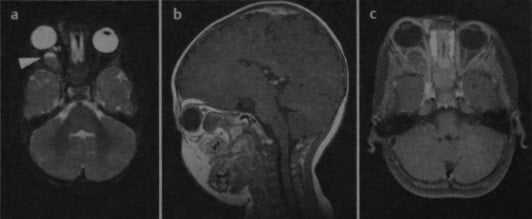

Гемангиома правой глазницы с кровоизлиянием в опухоль (стрелка: уровень жидкости). На Т1 - (а) и Т2-взвешенном изображении (b) визуализируется объемное образование, расположенное внутри конуса, образованного глазодвигательными мышцами. На П-взвешенном изображении (с) после введения гадолиния наблюдается незначительное усиление сигнала от опухоли.

КТ в горизонтальной плоскости с контрастированием: накапливающая контраст ретробульбарная гемангиома.